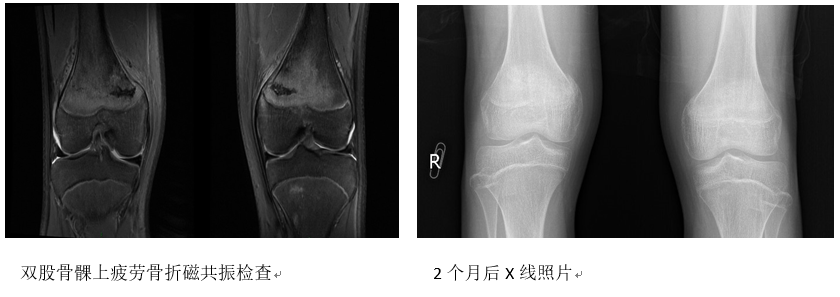

检查:形体瘦弱,双下肢无畸形,双股骨髁部有轻度肿胀与环形压痛,但无发红发热,纵向叩击疼痛不明显,无假关节形成,腹股沟无淋巴肿大。舌质稍暗红,苔薄白,脉弱。当即进行了双膝磁共振检查,确诊为双股骨髁上疲劳骨折。

治疗1周后双膝疼痛明显减轻,双膝上部肿胀消失;治疗2周后双膝无疼痛;1个半月后X线照片见双股骨骨折处对位对线好,骨折线模糊,骨痂生长明显,开始扶双拐步行;再半月后照片复查,显示骨折处对位对线好,有大量骨痂形成,去外固定护具,开始逐步活动膝关节和去拐。治疗3个月后,患儿膝关节活动完全恢复,能够徒步上学。